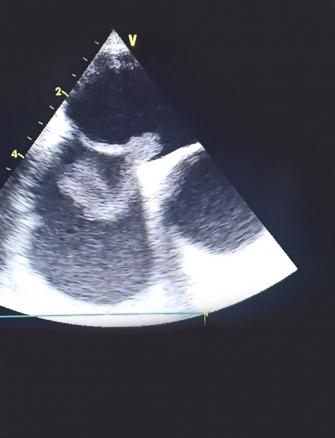

Cet homme de 37 ans était hospitalisé pour une hémiplégie gauche, 40 jours après ostéosynthèse d’une fracture du tibia droit. Son état hémodynamique et respiratoire était stable lors de son admission, avec des signes de thrombophlébite du membre inférieur droit et un rythme régulier sinusal à l’électrocardiogramme. La tomodensitométrie cérébrale montrait une plage ischémique temporo-pariétale droite. L’échocardiographie visualisait un thrombus mobile enclavé dans le foramen ovale perméable. Le patient était mis sous traitement anticoagulant ; une thrombectomie chirurgicale était réalisée avec fermeture du foramen ovale. Les suites opératoires étaient simples.

L’embolie paradoxale à travers un foramen ovale perméable est une cause rare d’accident vasculaire cérébral ischémique. Elle est due à l’embolisation systémique d’un caillot provenant de la circulation veineuse à travers le foramen ovale. Le diagnostic est posé devant la présence d’une thrombose veineuse, une preuve d’embolisation systémique et la démonstration échocardiographique d’une communication anormale entre les circulations droite et gauche.

La visualisation d’un thrombus enclavé dans le foramen ovale est exceptionnelle et augmente la mortalité et le taux de récidive ischémique liée à cette pathologie.1, 2

Le traitement curatif associe une anticoagulation efficace à une thrombectomie chirurgicale avec fermeture du foramen.